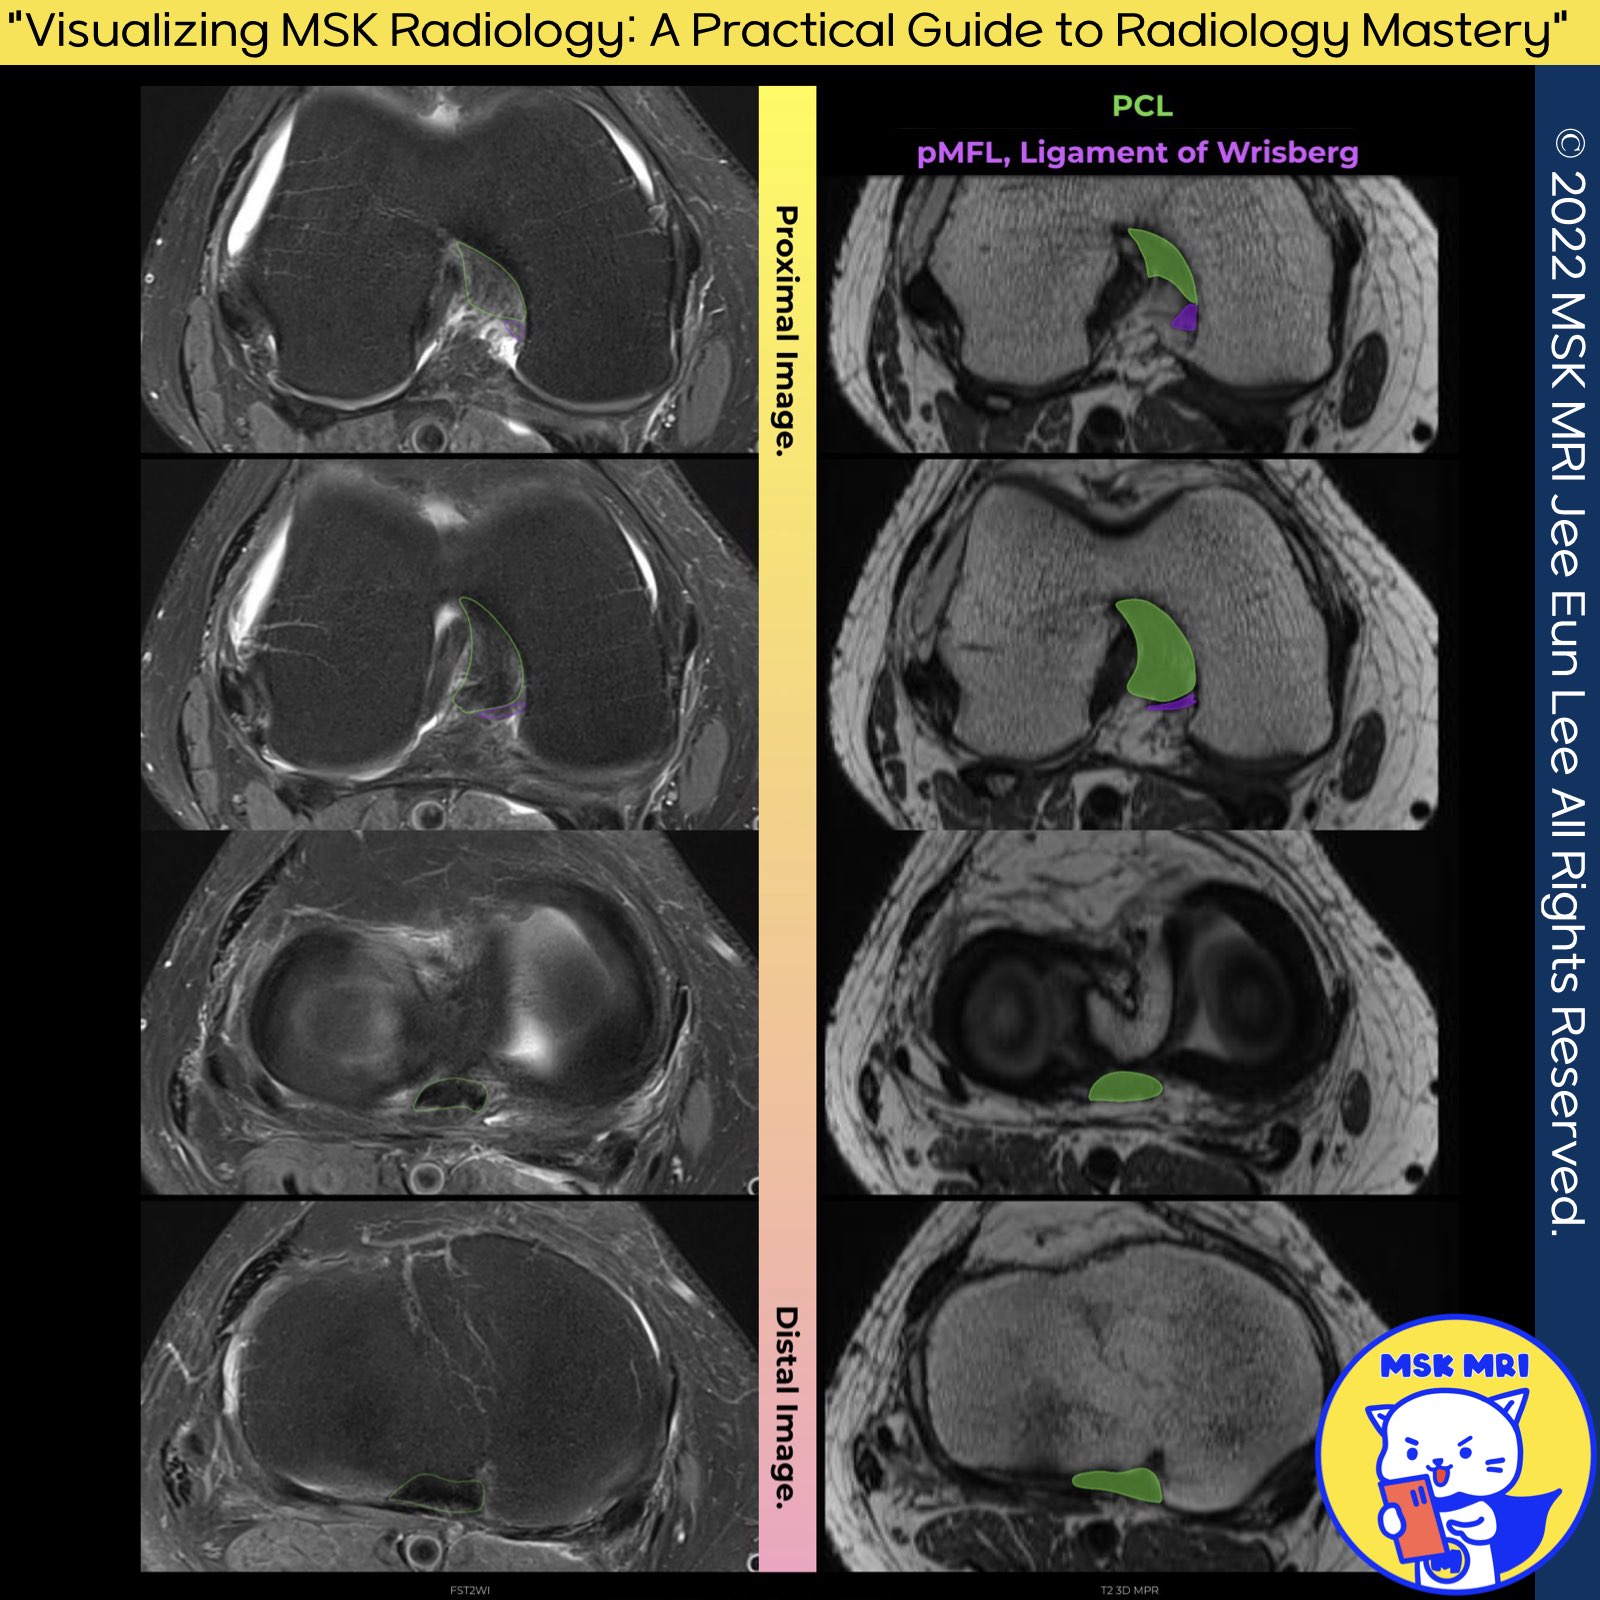

1️⃣ Anatomy of the PCL on axial Images:

- Axial images are particularly well suited for visualization of the vertical component and the coronal images for visualization of the horizontal component.

2️⃣ Meniscofemoral Ligaments (MFLs):

- The presence of the anterior and posterior MFL varies among individuals. The anterior MFL is observed in 20–75% of knees, whereas the posterior MFL appears in 70–100% of cases. Overall, at least one type of MFL is present in more than 90% of individuals.

- The MFLs attach near the Posterior Medial Bundle's (PMB) femoral attachment. Specifically, the posterior MFL attaches just proximal to it, and the anterior MFL attaches just distal, both exhibiting a circular cross-section.

3️⃣ Details on Meniscofemoral Ligaments:

- The attachment site of the anterior MFL (aMFL) varies, with 80% attaching distally to the PMB and the remaining 20% to the Anterolateral Bundle (ALB).

- The posterior MFL (pMFL) has a significant femoral attachment area, located proximal to the medial intercondylar ridge and PMB, and attaches distally to the posterior horn of the lateral meniscus.